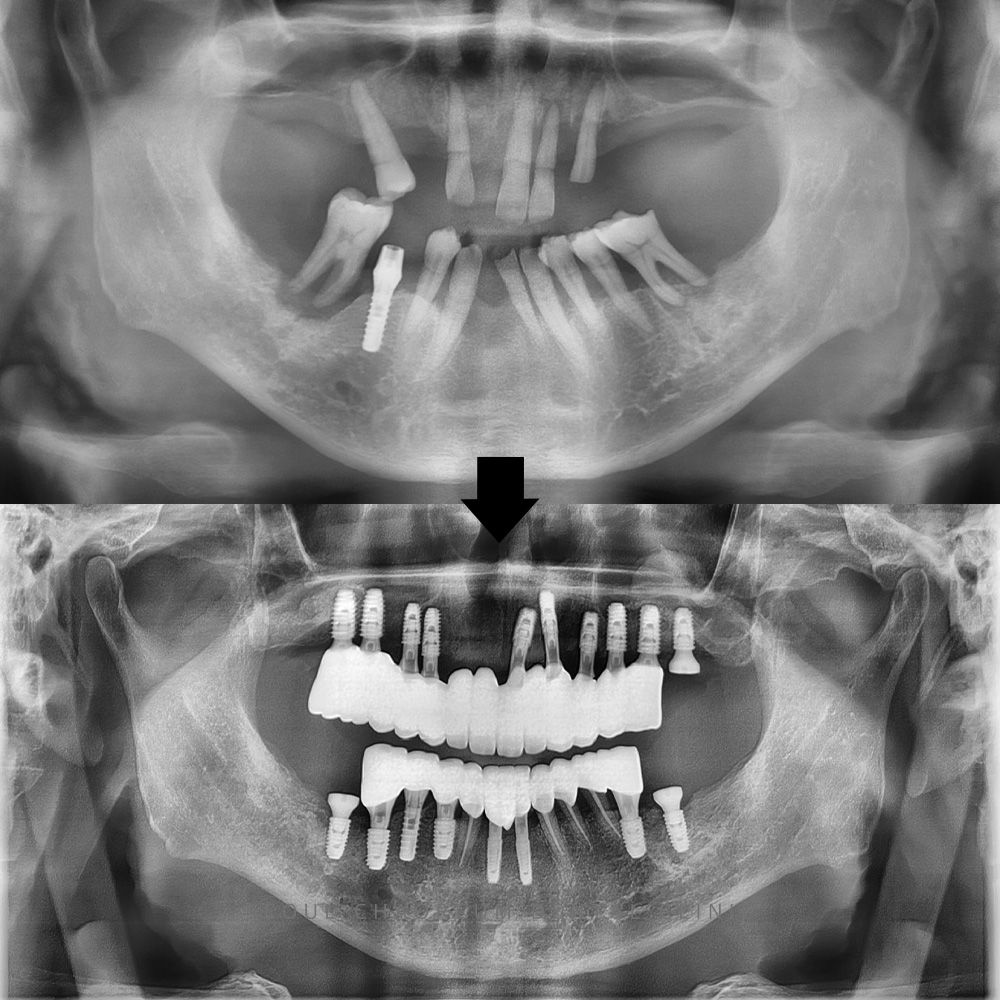

병점치과 전체적으로 임플란트 희망해요 치아가 상실된 상태로 오래 방치되면 주변 치아들이 빈 공간으로 쓰러지거나 위·아래로 정출되는 변화가 쉽게 나타납니다. 이러한 변위는 교합 불균형을 만들고 잇몸 건강을 악화시키며, 보철·임플란트…